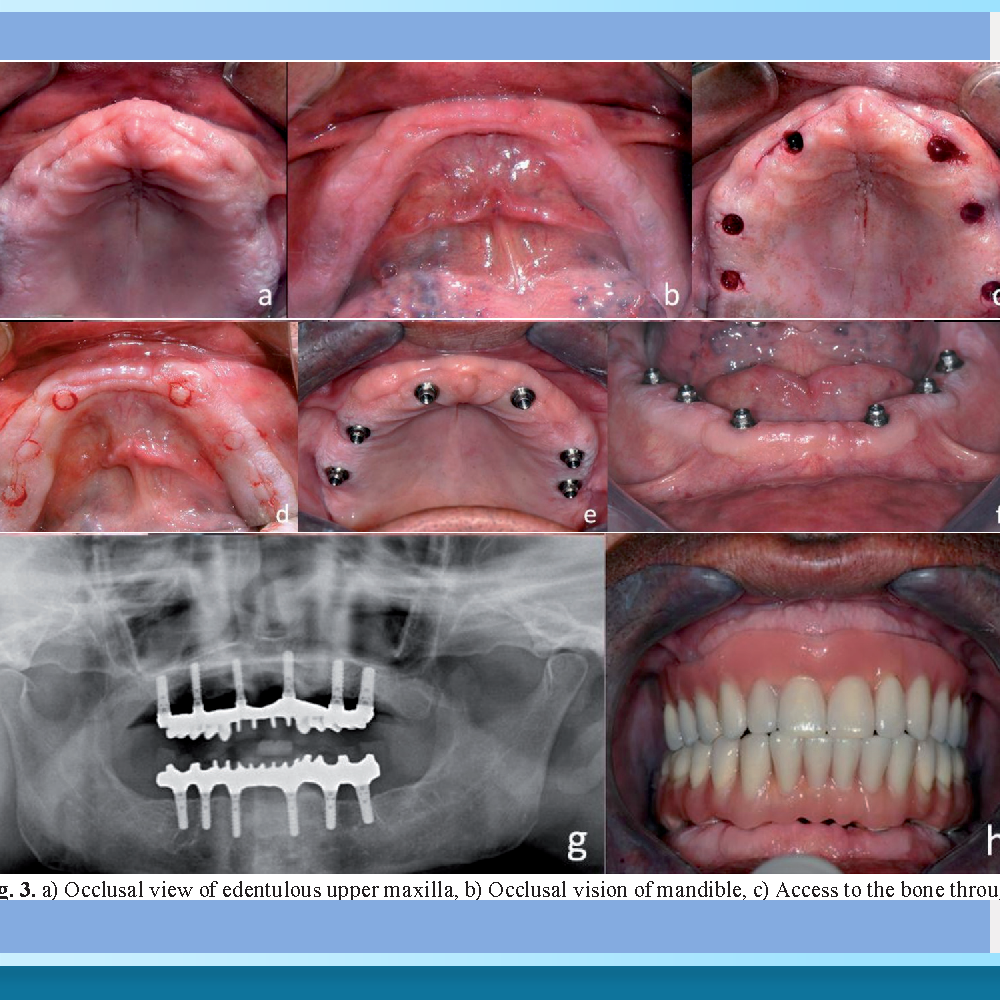

Ở cấp độ sơ khai nhất là trồng răng truyền thống (Free-hand). Bác sĩ hoàn toàn dựa vào cảm giác tay và kinh nghiệm để khoan xương. Để nhìn thấy xương, bác sĩ buộc phải rạch một đường dài trên nướu và lật vạt lợi ra. Phương pháp này phụ thuộc hoàn toàn vào trình độ bác sĩ, gây sưng đau nhiều sau phẫu thuật và tiềm ẩn sai số lớn nhất.

Đỉnh cao công nghệ hiện nay là Robot định vị (Dynamic Navigation). Đây là phương pháp “động”, cho phép bác sĩ quan sát trực tiếp mũi khoan đi trong xương. Các nghiên cứu đăng trên Tạp chí Nha khoa Implant Quốc tế đã chỉ ra rằng, công nghệ này giúp tăng độ chính xác gấp 11 lần so với làm tay truyền thống. Đặc biệt, bác sĩ có thể thực hiện ngay lập tức mà không cần chờ in máng, và có thể linh hoạt thay đổi vị trí cắm trụ ngay trong lúc mổ nếu phát hiện xương ở vị trí khác tốt hơn.

Thứ hai là hỗ trợ phẫu thuật không lật vạt (Flapless). Nhờ khả năng “nhìn xuyên thấu” mô mềm trên màn hình, bác sĩ có thể đưa mũi khoan xuyên qua nướu vào thẳng xương mà không cần dùng dao rạch lợi hay khâu vá. Điều này đồng nghĩa với việc bệnh nhân gần như không chảy máu, không sưng đau và có thể ăn ngon ngủ yên ngay sau khi về nhà.

Khi phẫu thuật bắt đầu, camera quang học sẽ liên tục theo dõi tay khoan của bác sĩ. Mọi thao tác khoan xương, đặt trụ đều được hiển thị trực quan trên màn hình lớn. Ngay sau khi trụ Implant được đặt ổn định, bác sĩ có thể lắp răng tạm ngay lập tức nhờ độ chính xác đã được đảm bảo.